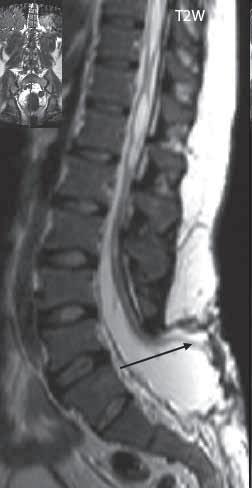

II.6 Vývojové vady míchy a páteře . . . . . . . . 426

II 6 1

Hydrosyringomyelie

Syndrom zadržené míchy a ztluštělého filum terminale (tethered spinal cord syndrome)

426

doba, kdy výše uvedený obor ovládalo pneumoencefalografické a perimyelografické vyšetření, se bude mladým lékařům zdát s trochou nadsázky tak vzdálená, jako vláda dinosaurů na naší planetě. Je logické, že na základě klinických zkušeností nové metody teprve najdou své optimální uplatnění, možná že některé naopak zaniknou objevem nových modalit.

Snahou byla „vyvážená“ učebnice v jednotlivých oblastech, i když jsme si vědomi, že výzkumné zaměření pracoviště jistě tuto snahu částečně ovlivní.